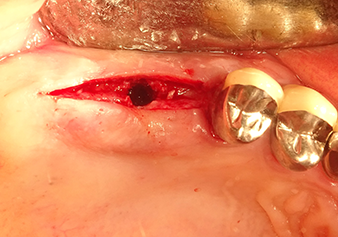

Implantation and prosthetic restoration

To move the augmentation material in the direction of the maxillary sinus atraumatically, the implant was inserted very slowly by hand (Fig. 9). In the process, the membrane was pushed in the cranial direction once again. After two months, the surgical site healed without irritation. Six months later, the x-ray check showed a significant increase in opacity as an indication of ossification (Fig. 10). The prosthetic restoration was carried out with a metal-ceramic crown.